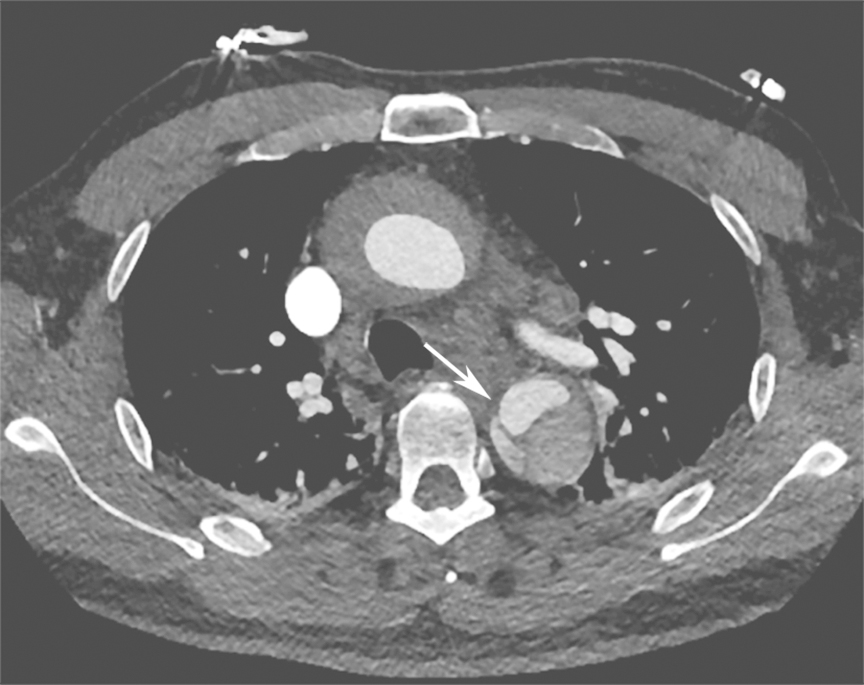

入院后紧急行血管螺旋CT扫描+三维重建,以明确主动脉病变。血管螺旋CT扫描+三维重建如图2所示。降主动脉至腹主动脉夹层动脉瘤并壁间血肿形成(累及主动脉弓至肾动脉开口平面)。升主动脉管径约4.9cm。主动脉弓与降主动脉弥漫管腔增粗,周围可见弥漫壁间血肿形成,向下延伸至肾动脉平面。主动脉弓上三大分支开口与显影良好。主动脉弓外径为5.4cm,内径约3.8cm。降主动脉外径为7.5cm,内径为4.8cm。气管隆嵴下平面降主动脉左前壁局限性钙化上方有一个溃疡,溃疡内有少量对比剂充盈。胸主动脉下段向右侧明显迂曲。腹主动脉与肾动脉平面上方可见内膜片与真假腔形成,假腔内有少量造影剂充填。腹腔干动脉和肠系膜上动脉开口未见受累。右肾动脉开口部分受累,左肾动脉开口未见受累。腹主动脉下段、双侧髂内外动脉血管形态良好。双侧胸腔中等量积(血)液(图3箭头处)。

图2主动脉CT螺旋扫描+三维重建

如果在某一层面看到管腔中的低密度线影不连续,或是对比剂将两个管腔沟通,就可以判定夹层破口的位置(图5)。

图5主动脉夹层破口位置